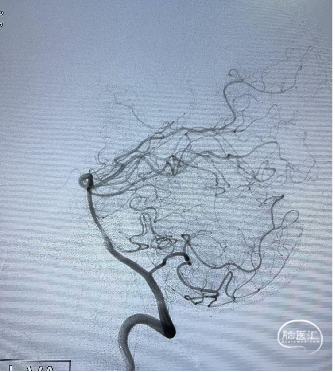

![]() 术后影像

术后影像

术后多角度造影显示动脉瘤致密填塞,其他血管显影正常。术后CT无异常,mRS 0 分。

术后CT未见异常,mRS 0 分,无神经系统症状和体征,计划术后半年后复查DSA